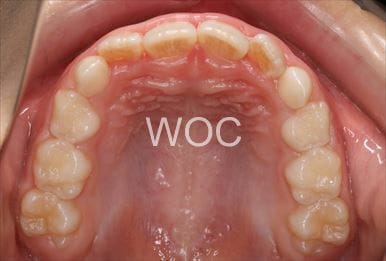

治療前1

治療前2

治療前3

治療前4

治療前5